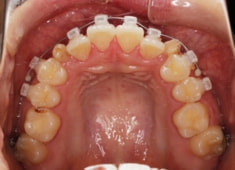

症例紹介

先天欠如歯両側上顎3番

治療法:フルパッシブブラケット:T21

治療開始時

治療中